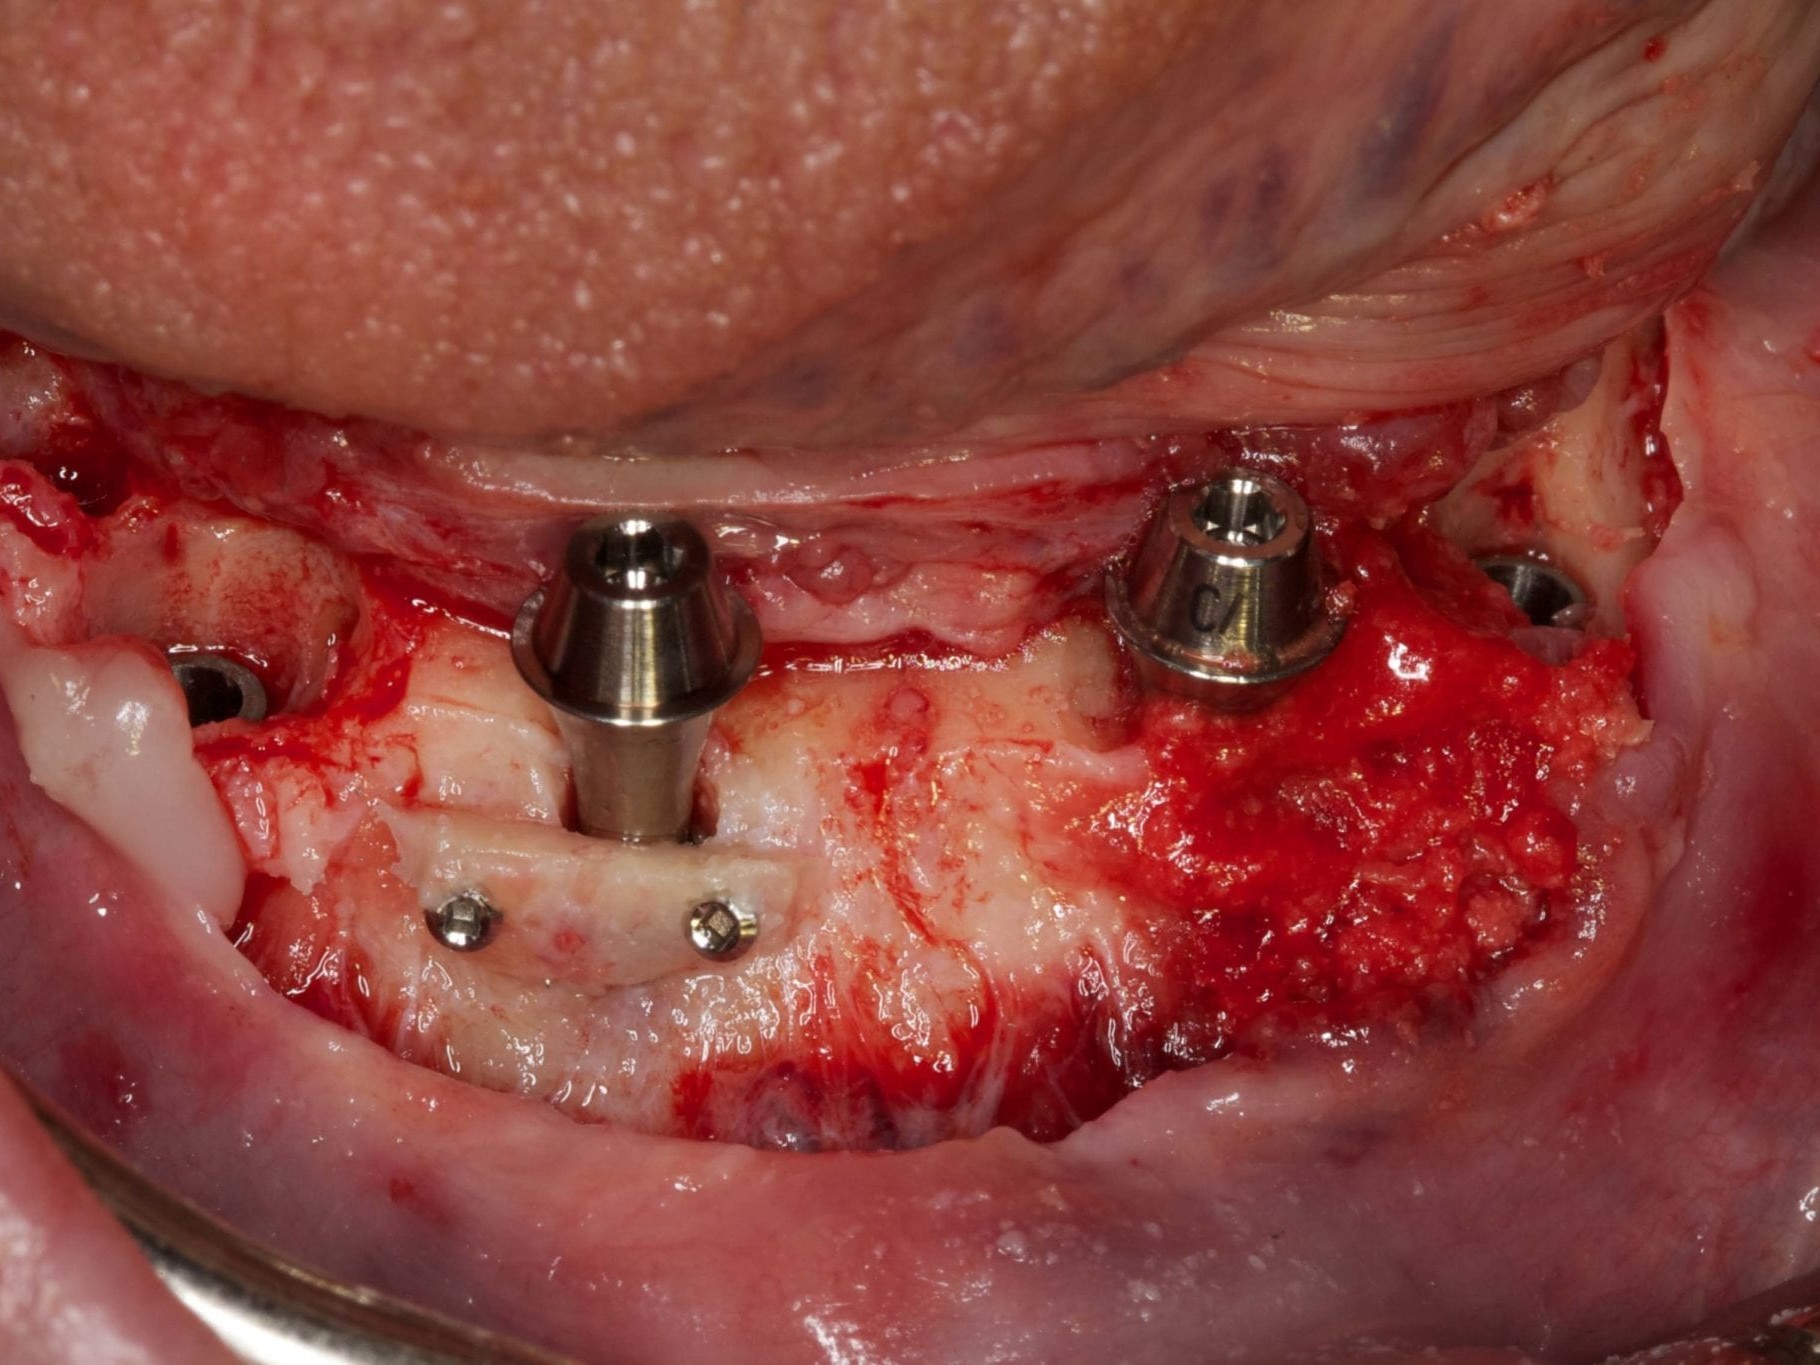

Für die Allgemeinanästhesie erfolgte zunächst die zusätzliche Gabe eines typischen Infiltrationsanästhetikums. Intravenös wurde unmittelbar präoperativ das Antibiotikum Clindamycin 600 mg gegeben. Abbildung 7 zeigt die klinische Ausgangssituation linksseitig. Nach der vorsichtigen Durchtrennung der Brückenkonstruktion (Abb. 8) jeweils vor der Krone auf den Blattimplantaten und Entfernung der nicht erhaltungswürdigen Zähne 44 bis 33 samt ihrer Überkronung (Abb. 9) wurde der Mukoperiostlappen vestibulär wie lingual passend zur erstellten Schablone präpariert und die Bohrschablone in ihrer finalen Lage eingebracht (Abb. 10). Zunächst erfolgte die Insertion der angulierten Implantate Ankylos ® C/X-Implantate (Durchmesser 3,5 mm) der Länge 14 mm in regio 034 (Abb. 11 und 12) und 044. Danach wurden in den Positionen 032 und 042 jeweils ein weiteres Ankylos ® C/X –A-Implantat mit gleicher Länge und Durchmesser inseriert (Abb. 13). Sämtliche entfernten Knochenpartikel und auch Bohrspäne wurden akribisch asserviert. In den Positionen 032 und 042 wurden Ankylos ® Balance Basisaufbauten C/ (GH 3,0 / Ø 5,5 mm, Kopfhöhe 2,4 mm) mit 15 N/cm eingeschraubt. Anschließend hat der Zahntechniker mittels der Ankylos ® Modellierhilfskappenfür den Balance Basisaufbau Retentionskappen hergestellt, die mit 25 N/cm eingebracht wurden (Abb. 14). Am Implantat regio 042 wurde der Knochen in Schalentechnik nach vestibulär aufgebaut (Abb. 15)⁹,¹⁰. Im nächsten Schritt haben wir die angulierten Ankylos ® Balance Basisaufbauten C (nicht indexierte Abutments) in Regio 034 und 044 (GH 3,0, A30 / Ø 4,2 mm, Kopfhöhe 1,3 mm) ausgerichtet und ihren spezifischen Vorgaben entsprechend eingebracht (Abb. 16). Nachdem sich alle erforderlichen prothetischen Implantatbauteile in situ befanden (Abb. 17), erfolgte die Überprüfung und geringfügige Anpassung des im Vorfeld digital erstellten Sofortprovisoriums. Im Anschluss wurden die leeren Alveolen und Knochendefekte mit dem gewonnenen autologen partikulären Material aufgefüllt. Dann erfolgte der typische Naht-Wund-Verschluss mit Einzelknopfnähten eines resorbierbaren Nahtmaterials (Abb. 18). Nachdem die Patientin aus der Vollnarkose erwacht war und ihre motorischen Fähigkeiten wiedererlangt hatte, wurde das Sofortprovisorium eingesetzt und in Okklusion gebracht. In dieser Position wurden die Retentionskappen über ein selbsthärtendes fluoreszierendes kaltpolymerisierendes Paste-Kartuschensystem fixiert. Anschließend erfolgte die extraorale Versäuberung des Interimszahnersatzes. Nach Refixierung des Sofortprovisoriums in der Mundhöhle (Abb. 19 und 20) und dem Verschluss der Schraubenkanäle mit Kunststoff erfolgte die radiologische Kontrolluntersuchung (Abb. 21).